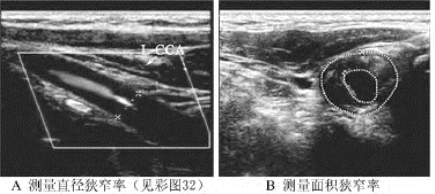

1.26.4四、动脉闭塞性疾病

1.26.11十一、血管功能超声评价的新技术